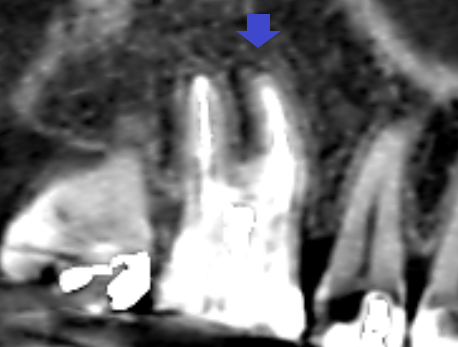

上顎第一大臼歯の初診時の矢状断のCT画像です。

赤い矢印の先の近心頬側根の先に膿の影がみられます。